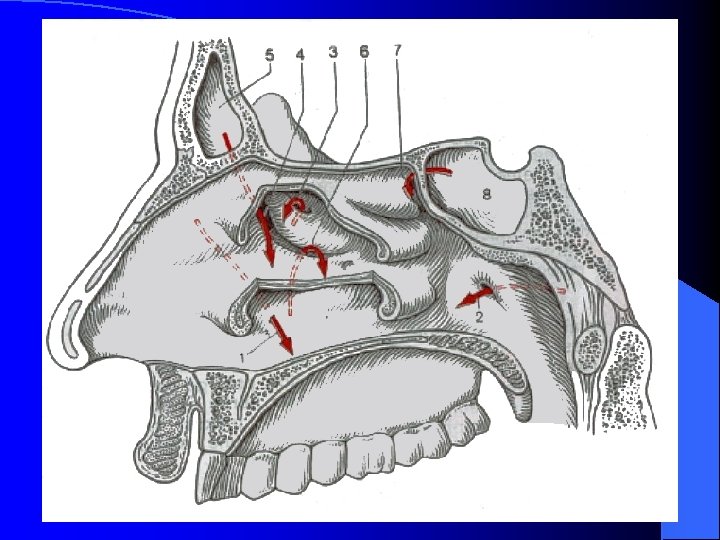

ANATOMIE DES CAVITES RHINO SINUSIENNES SINUS MAXILLAIRE Le plus volumineux Pyramide quadrangulaire à base médiale et à sommet latéral Drainage par le méat moyen dans la fosse nasale

ANATOMIE DES CAVITES RHINO SINUSIENNES SINUS FRONTAL Le plus antérieur Pneumatisation de l’épaisseur de l’os frontal Variations anatomiques Drainage par le canal naso-frontal

ANATOMIE DES CAVITES RHINO SINUSIENNES LABYRINTHE ETHMOIDAL Parallélépipède rectangle pluricellulaire Drainage individuel de chaque cellule dans la fosse nasale

ANATOMIE DES CAVITES RHINO SINUSIENNES SINUS SPHENOIDAL Sinus le plus profondément situé dans la face Forme grossièrement cubique Drainage en regard de la queue du cornet supérieur (récessus sphéno-éthmoïdal)